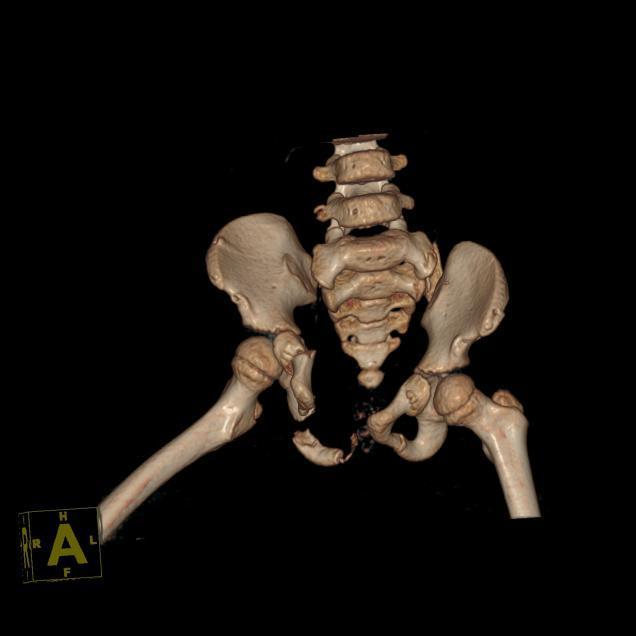

盆环完全断裂,多处粉碎性骨折、脱位、移位,尿道断裂、外阴撕裂……近日一起交通事故中,广西一名4岁女童小花(化名)盆腹部遭到碾压,骨盆几近“散架”,但孩子依然顽强地活了下来。如此重创让见惯了大阵仗的医生们心痛不已,“克服万难也要修复好!”面对复杂严重的伤势,南医三院创伤骨科、妇科、泌尿外科专家在手术台上紧密合作,接力施救,奋战7个小时,终于成功完成了“拼图”式的精准修复。

首先由樊仕才团队主刀,当骨折部位暴露在手术视野中,医生们不禁为这个孩子捏了一把汗:耻骨联合分离,左侧骶髂关节向前方脱位,双侧耻骨、髂骨多处骨折,断端移位,左侧腰骶干神经出现根性撕脱,左髋部及大腿外侧发现大量皮下积血、积液……克服一切困难,也要帮她“拼”回去!

术前